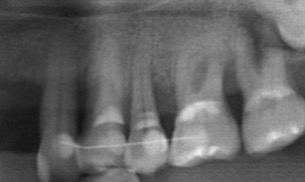

微創牙周再生-陳珮儀醫師

牙齒周邊因為破壞所喪失的骨頭,放置牙周再生材料,重建喪失的牙周

治療前